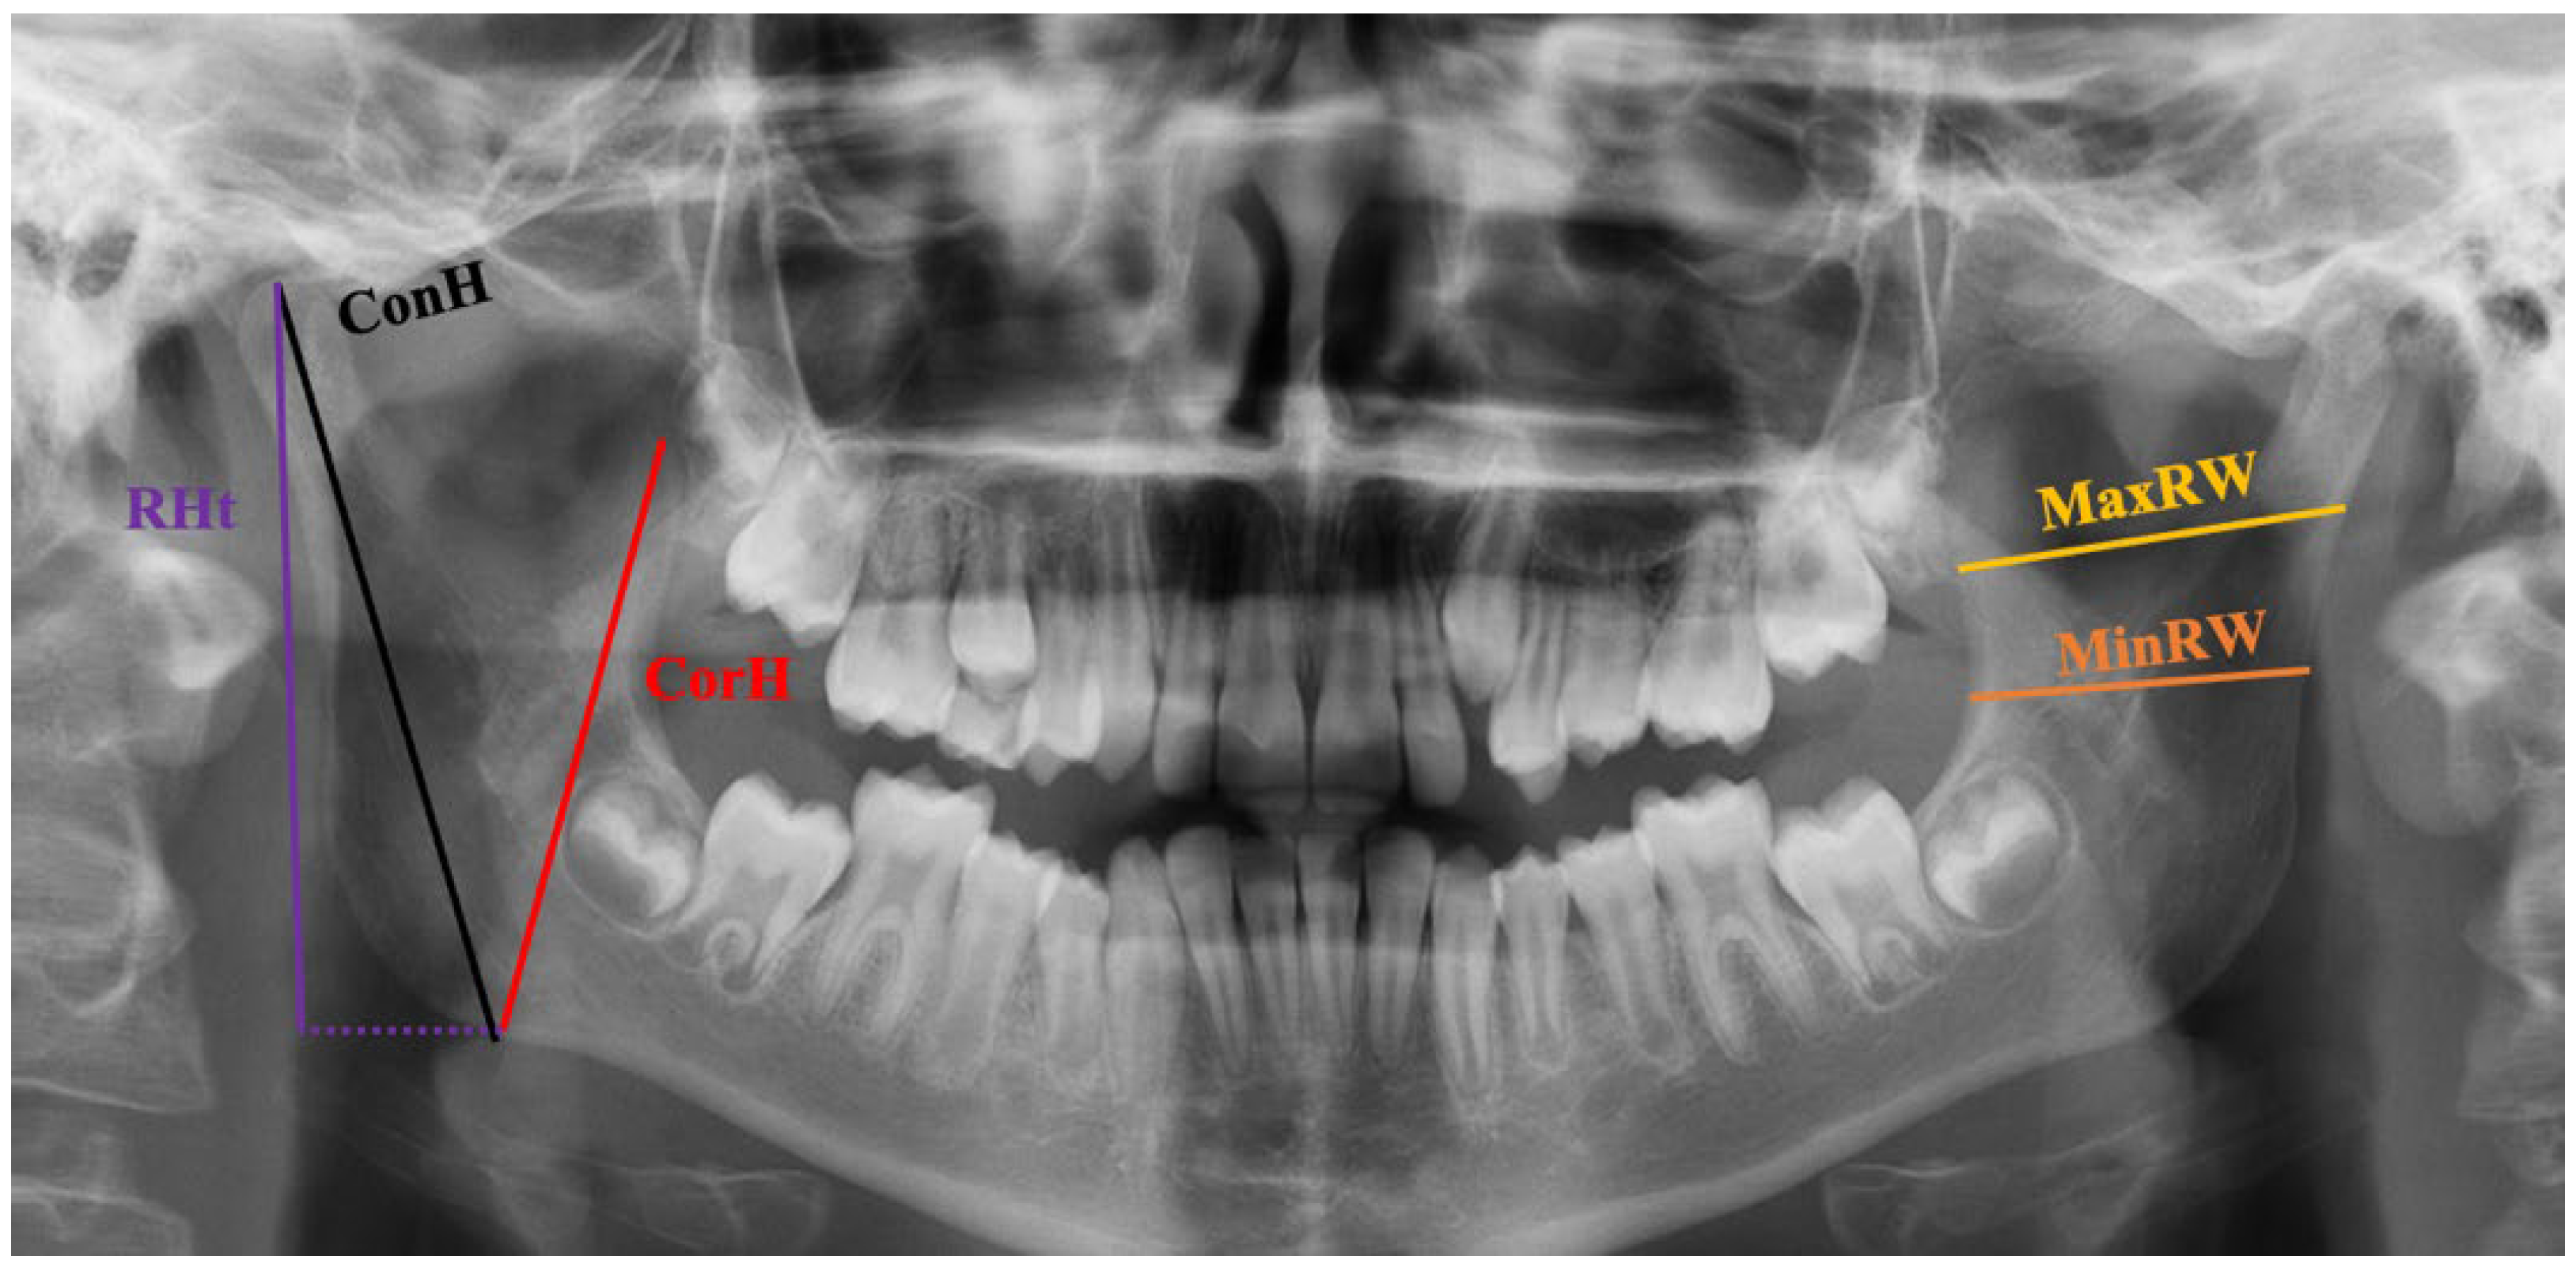

2.7. Morphometric Measurements

| Condylar height | r | 0.758 | 0.753 | 0.802 |

| p | <0.001 | <0.001 | <0.001 | |

| Coronoid height | r | 0.620 | 0.652 | 0.671 |

| Ramus height | r | 0.700 | 0.712 | 0.763 |

| Maximum ramus height | r | 0.579 | 0.561 | 0.580 |

| Minimum ramus height | r | 0.325 | 0.335 | 0.333 |

| p | <0.001 | <0.001 | <0.001 |